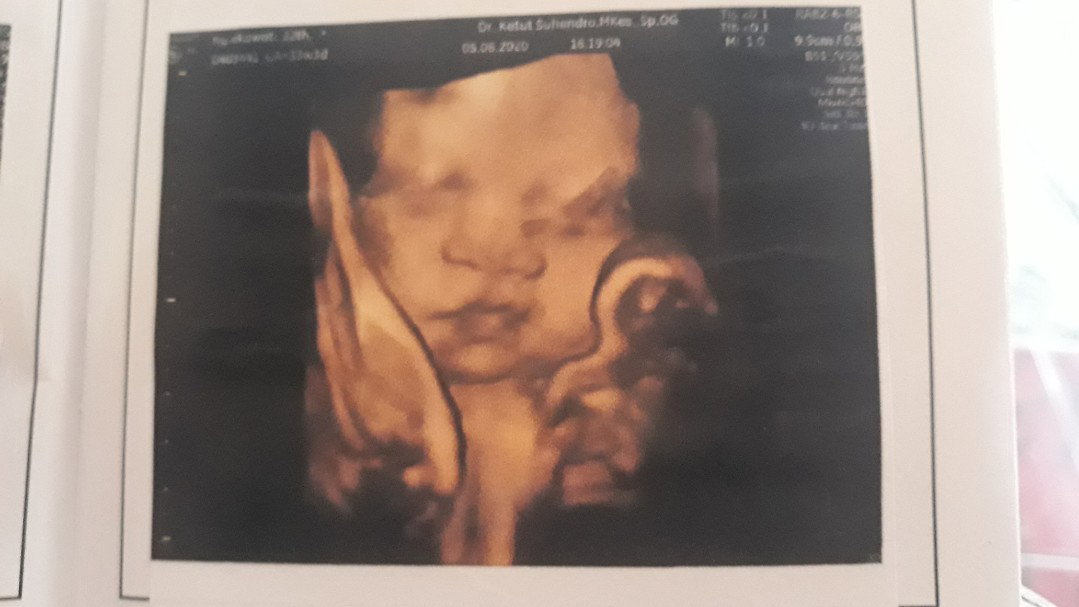

Posisi Bayi Melintang

Bun saya kemarin USG ke dokter kata dokternya posisi bayi saya melintang (kepala diperut bawah sebelah kanan ,kaki sering gerak diperut atas sebelah kiri) ,usia kehamilan saya 33 minggu ,ada saran yg pernah ngalamin hal yg sama ,apakah bisa lahiran normal? Minta tips nya bun ,soalnya sedikit worry karna dr nya bilangnya kehamilan pertama gaboleh melintang seharusnya?